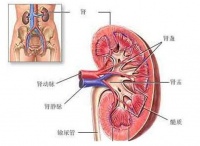

肾囊肿(renal cyst,cyst of kidney)是肾脏内出现大小不等的与外界不相通的囊性肿块的总称,也叫做肾囊性疾病(cystic diseases of the kidney)。常见的肾囊肿可分为多囊肾、单纯性肾囊肿和获得性肾囊肿、髓质海绵肾及肾盂旁囊肿等。

肾囊肿是最常见的肾脏异常,任何年龄均可发生,但2/3以上的患者见于50岁以上中老年人,被认为是衰老的改变。肾囊肿常偶然被发现,大多数肾囊肿不引起任何症状。如引起腰部胀痛或尿频、尿急、尿痛、尿血等泌尿系感染时,一般囊肿均较大,直径在5cm以上。对于小的肾囊肿,无症状时不需要做任何治疗,但要定期复查,观察囊肿是否继续增大。

肾囊肿是一种先天性遗传性疾病,肾脏实质内充满数不清大小不等的与外界不相通的圆形囊肿,囊内含有液体,小的肉眼看不到,大的可有数厘米,故称之为多囊肾。表现为夜尿增多、腰痛、高血压等。尿检有血尿、少量蛋白尿,常会缓慢地发展成为慢性肾衰。有10%的人伴有肾结石,30%的人伴有多囊肝。有经验的医生借助B超、静脉肾盂造影可确诊。

单纯性肾囊肿可能是一种先天性异常,是单侧或双侧肾及有一个或数个大小不等的圆形与外界不相通的囊腔,多数是单侧,故称单纯性肾囊肿。其发病率可随便年龄增长而增高,50岁以上的人做B超,有50%可以发现这种囊肿。借助B超、CT可确诊。

囊肿可以是一侧也可是二侧,每个肾脏有一个或少数几个囊肿。囊肿一般孤立呈球形,位于肾皮质浅表者可改变肾脏外形,也可位于皮质深层或髓质,直径0.5~1㎝,也可3~8㎝,囊壁薄而透明,内含草黄色液体,较粘稠,如有过炎症,囊壁可增厚,纤维化甚至钙化。囊肿与肾盂不相通,壁内衬以单层扁平上皮细胞。